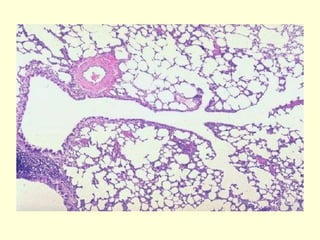

Bronquíolos

Los bronquíolos son vías aéreas de

conducción que miden 1 mm de diámetro o

menos.

Los bronquíolos más grandes se conocen

como bronquíolo propiamente dicho y son

ramas de los bronquios segmentarios.

Estos conductos sufren ramificaciones

consecutivas para dar origen a los

bronquíolos terminales, que son más

pequeños y también se ramifican.

Por último, los bronquíolos terminales dan

origen a los bronquíolos respiratorios.

Bronquíolo terminal

Están revestidos por un epitelio cúbico

simple en el cual hay células de Clara

dispersas entre las células ciliadas.

La capa de músculo liso y el diámetro de

este bronquíolo es menor que en el

propiamente dicho y por lo tanto lo

característico frente al microscopio es ver

una estructura circular bien definida.

Bronquíolo respiratorio

Se caracteriza por tener su pared

bronquiolar interrumpida por alvéolos y es

aquí donde comienza el intercambio

gaseoso.

Marca el comienzo de la porción

respiratoria y el fin del sector de

conducción del aparato respiratorio.

Alvéolos

 Los alvéolos son los espacios aéreos terminales

del aparato respiratorio y las estructuras en las

que se produce el intercambio gaseoso entre el

aire y la sangre (hematosis).

 Cada alvéolo está rodeado por una red de

capilares que ponen la sangre muy cerca del aire

inspirado que está en la luz alveolar.

 En cada pulmón de adulto hay entre 150 y 250

millones de alvéolos; la extensión de su superficie

interna combinada es de alrededor de 75 m2, más

o menos las dimensiones de una cancha de tenis.

Los conductos alveolares son vías aéreas

alargadas que casi no tienen paredes sino

sólo alvéolos como sus límites periféricos.

Los sacos alveolares son espacios

rodeados por cúmulos de alvéolos. Los

alvéolos circundantes se abren hacia estos

espacios.

Los alvéolos están rodeados y separados

unos de otros por una finísima capa de tejido

conectivo (tabique alveolar) que contiene

capilares sanguíneos.